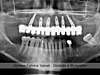

Panoramique de début des soins 06/2008

Début des soins du 16/05/2008